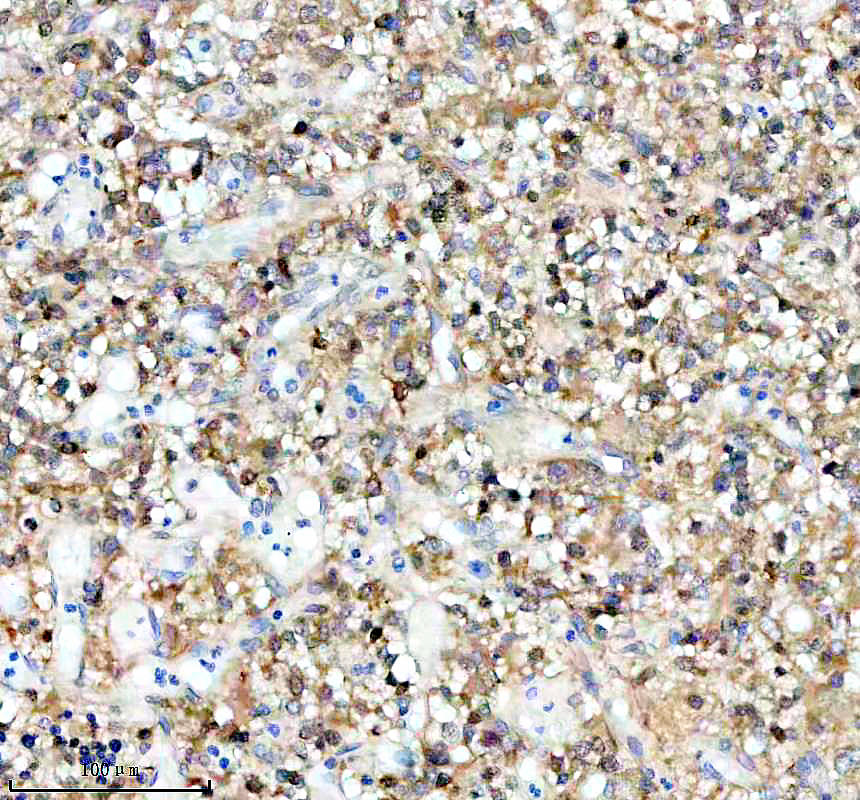

IHC analysis of BNIP3L using anti-BNIP3L antibody (BM5174) .

BNIP3L was detected in a paraffin-embedded section of human ovarian cancer tissue. The tissue section was incubated with rabbit anti-BNIP3L Antibody (BM5174) at a dilution of 1:200 and developed using HRP Conjugated Rabbit IgG Super Vision Assay Kit (Catalog # SV0002) with DAB (Catalog # AR1027) as the chromogen.

IHC analysis of BNIP3L using anti-BNIP3L antibody (BM5174) .

BNIP3L was detected in a paraffin-embedded section of human ovarian cancer tissue. The tissue section was incubated with rabbit anti-BNIP3L Antibody (BM5174) at a dilution of 1:200 and developed using HRP Conjugated Rabbit IgG Super Vision Assay Kit (Catalog # SV0002) with DAB (Catalog # AR1027) as the chromogen.